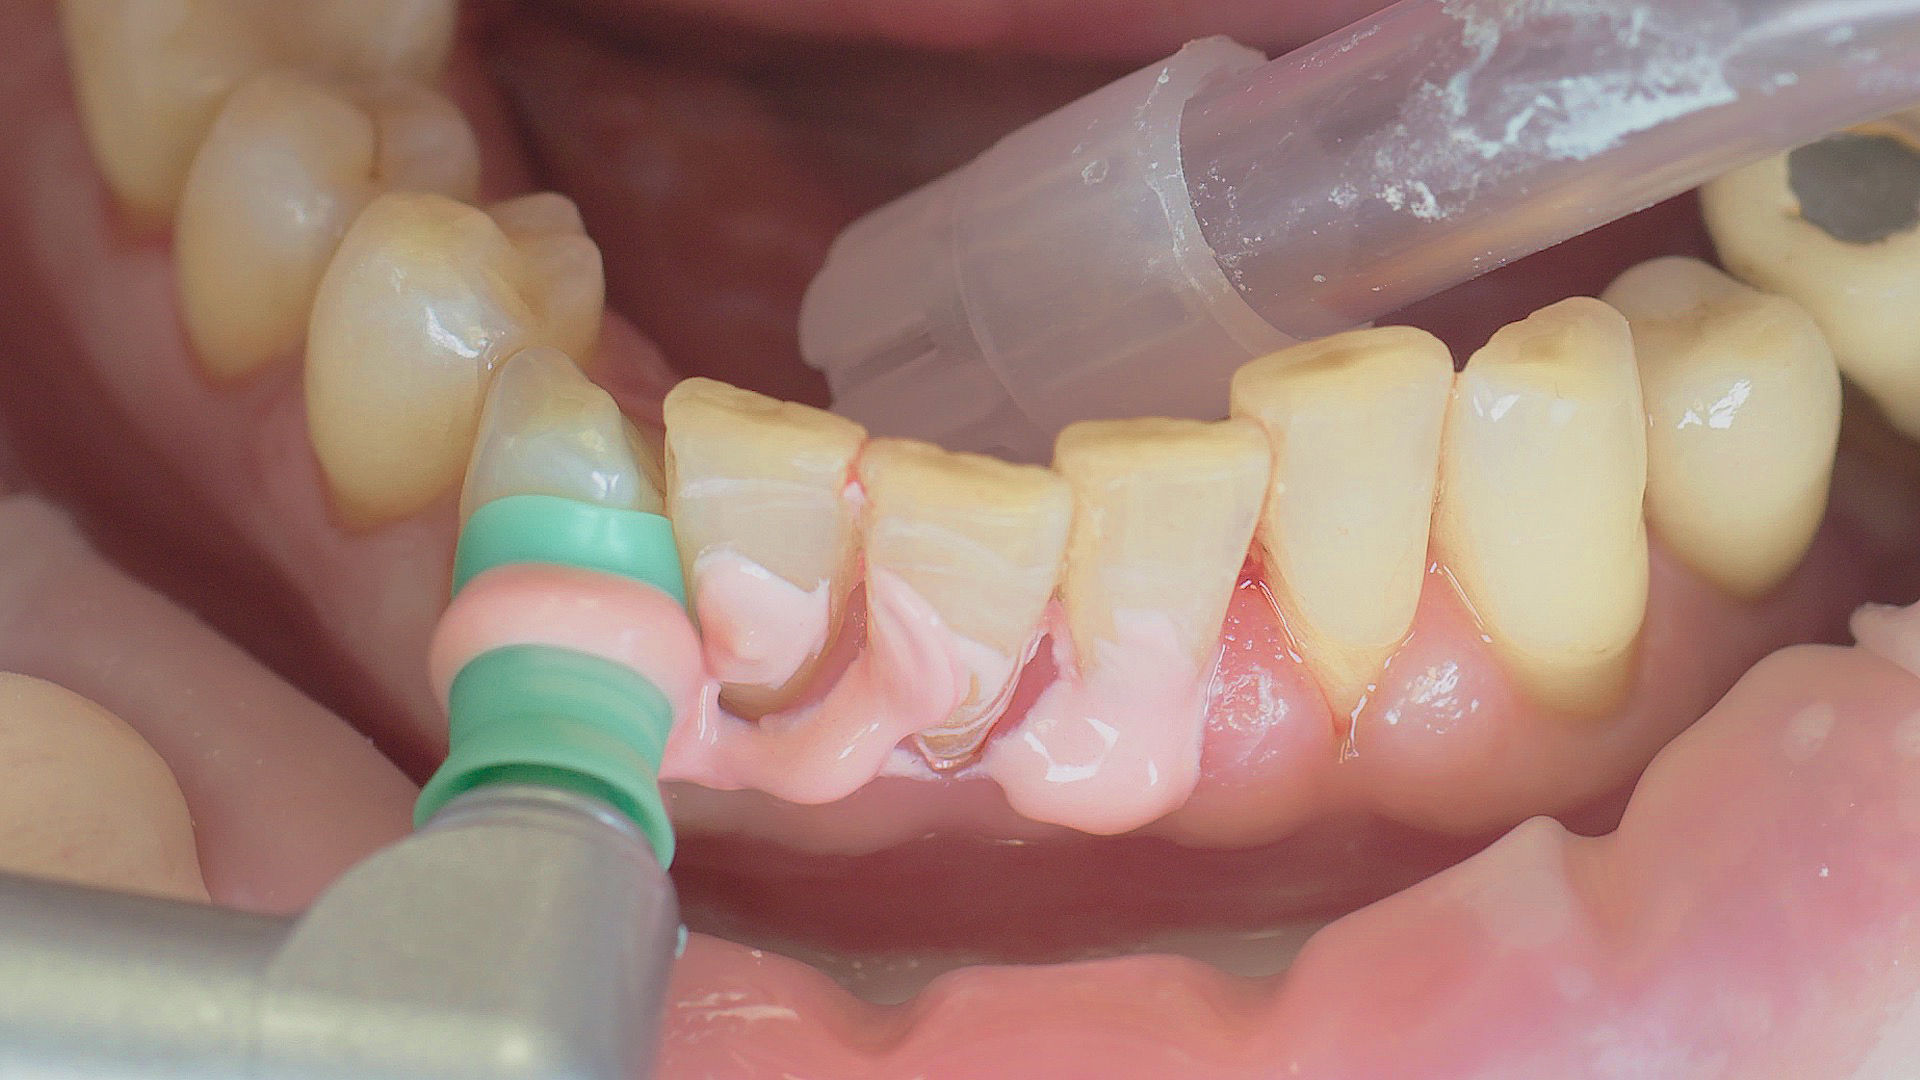

Lors des soins postopératoires ou d’un traitement non chirurgical, les implants et les superstructures peuvent être nettoyés à l’aide d’appareils à ultrasons et d’instruments en plastique spécifiques.

Fig. 3 : Lors des soins postopératoires ou d’un traitement non chirurgical, les implants et les superstructures peuvent être nettoyés à l’aide d’appareils à ultrasons et d’instruments en plastique spécifiques.

Lorsqu’il est sain, le tissu péri-implantaire ne montre aucun signe de rougeur, de gonflement ou de saignement et l’examen ne révèle aucune formation de pus.[5] À partir du document de consensus, le Pr Giovanni Salvi a justifié l’importance d’un examen régulier — de préférence à l'aide d’une sonde flexible, car les éléments de l'implant ont tendance à gêner l'accès au site d’intervention.[5] Dans le cas d’une mucite ou d’une péri-implantite initiale déjà présentes, il convient dans un premier temps de tenter d’éliminer par une méthode non chirurgicale les dépôts durs et le biofilm. Pour ce faire, on utilise des instruments à ultrasons et spéciaux conçus pour protéger l'implant (Fig. 3 ; détartreur piézo Tigon+ avec 1I, W&H). En l'absence de rémission, la fréquence de suivi doit être augmentée. Toutefois, aucune recommandation spécifique, applicable au cas par cas, n’a encore été donnée dans ce contexte.[15]